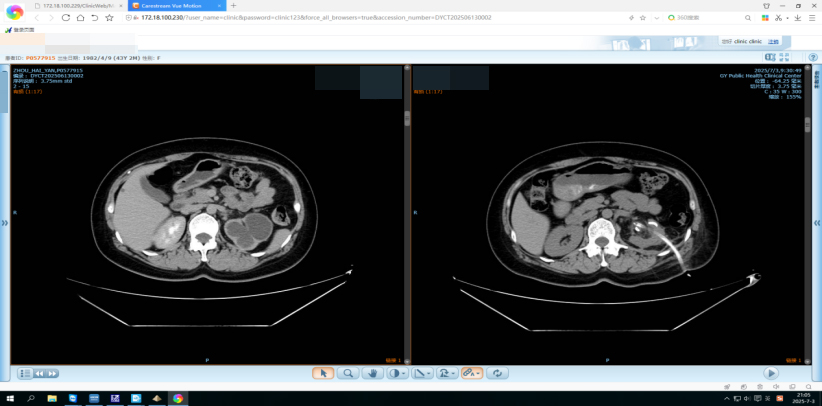

“她的腎盞因為結核的問題,幾乎完全‘封死’,藥進不去,積水排不出,就像氣球越吹越大!”泌尿外科皮主任指著CT片解釋,在謹慎討論過患者的具體情況后,皮生明主任帶領科室成員,為該患者量身定制了一個“三步走”方案:1、精準“打洞” ——在腰部建立微創(chuàng)通道,清除結核膿灶,局部灌注高濃度藥物,藥直接送到‘戰(zhàn)場’,濃度比口服高幾十倍,能有效清除結核病灶;2、雙鏡合璧—— 經皮腎鏡“自上而下” 輸尿管軟鏡“自下而上”,如同隧道施工雙向對接,光源交匯處,就是閉鎖腎盞的“命門”;3、重建“生命水路”——用支架撐開狹窄的腎盞頸,讓積水和尿液回歸正常通路,腎盞和腎盂終于“握手言和”!

患者術前術后影像對比圖

術后第三天,趙女士就能自主下床活動。最新復查顯示,左腎積水消失,形態(tài)恢復正常?!霸瓉碓诒本┦中g,積水問題一直沒有解決。這里雙鏡一照,每一步都看得清清楚楚!病人少受罪,治療也更精準!”她豎起大拇指。